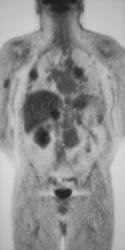

Recurrent Renal Cell Carcinoma in Nephrectomy Bed